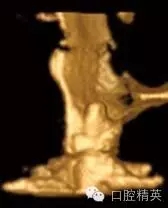

圖1c:術(shù)后用ICATCBCT進(jìn)行三維立體效果再現(xiàn),顯示種植體穿入上頜竇的實(shí)踐情況

圖3a:術(shù)后的三維影像重建給外科醫(yī)生對(duì)手術(shù)入路的回顧以提示。對(duì)于這一病例進(jìn)行了Caldwell-Luc術(shù)式,用球鉆在上頜竇側(cè)壁做一窗口,直接入路取出種植體。